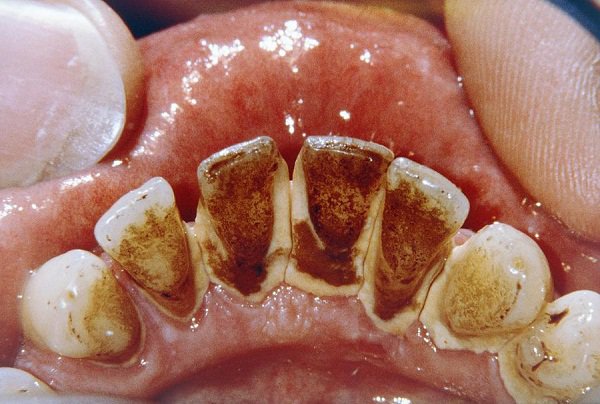

🔴 Cao răng màu đen: Màu sắc xấu xí này được coi như là mức phát triển cao nhất của cao răng. Nếu bạn tiếp tục “sống chung” với cao răng huyết thanh bên trên, phót lờ tình trạng viêm lợi, chảy máu và chảy mủ thường xuyên trong khoang miệng thì cao răng lúc này sẽ biến thành màu đen. Ngoài ra, một số thói quen xấu như thường xuyên hút thuốc hay ăn các thực phẩm tối màu cũng khiến cao răng chuyển sang màu đen.

Trong một số trường hợp, cao răng màu đen cũng có thể xuất phát từ nguyên nhân sâu răng. Đây là mức màu sắc báo động, cảnh báo về những nguy hiểm liên quan đến sức khỏe răng miệng mà bạn cần lưu ý và nhanh chóng có biện pháp khắc phục kịp thời trước khi chúng gây ra biến chứng.

➤ Cao răng màu đen là tình trạng báo động, nó hoàn toàn có thể cướp đi tất cả những chiếc răng trên khuôn hàm của bạn chỉ trong một thời gian ngắn. Cũng giống như cao răng huyết thanh, cao răng màu đen gây ra một loạt biến chứng nguy hiểm, thậm chí còn ảnh hưởng đến cả sức khỏe.